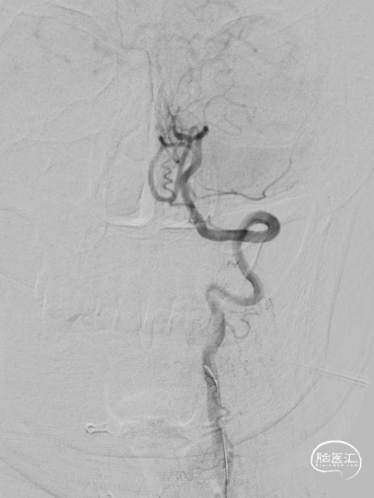

全脑血管造影DSA:双侧椎动脉起始段狭窄。远端供血不足。

患者双侧椎动脉均狭窄,左侧重度狭窄。左侧椎动脉充盈延迟、血流瘀滞,为闭塞前表现。所以权衡双侧椎动脉狭窄血管成型术的指征,优先处理左侧椎动脉起始段狭窄。为预防急性后循环缺血性卒中,在家属知情同意前提下行支架成形术。

该患者双侧椎动脉起始段均狭窄,左侧更为严重,为闭塞前病变。为预防致死致残性脑卒中,行左侧椎动脉起始段支架植入术。选择Bridge椎动脉雷帕霉素靶向洗脱支架。该支架的雷帕霉素涂层可向血管内膜靶向释放药物,有效抑制支架植入术后的内膜增生,减少远期支架内再狭窄几率。同时也能有效改善后循环的血供,减少后循环脑卒中发生机会。该支架是治疗椎动脉狭窄的良好选择。